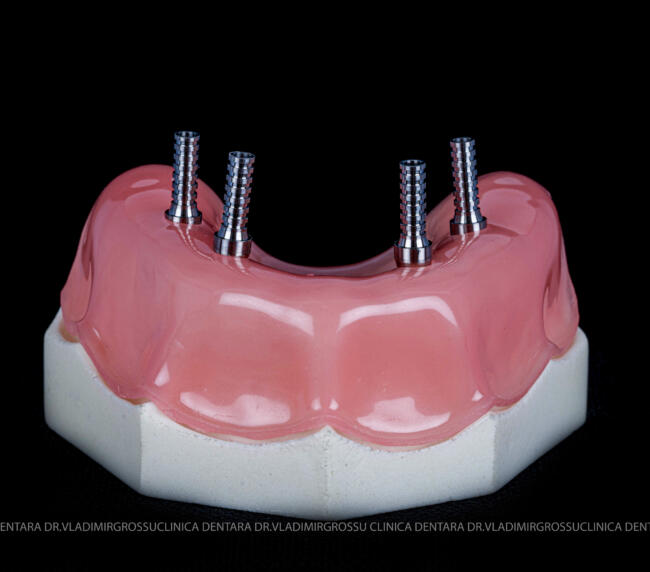

studii științifice.În cazurile de atrofie osoasă severă, când inserarea implanturilor în zonele laterale nu este posibilă fără adăugare osoasă, conceptul All-on-4 prevede plasarea implanturilor în unghiuri strategice pentru a evita zonele deficitare. Astfel, două implanturi sunt plasate în zona incisivilor laterali, iar alte două în zona premolarilor.

- 4 implanturi;

- 2 multiunit-uri drepte și 2 multiunit-uri angulate, conform necesităților protetice;

- 4 abutment-uri provizorii pe multiunit-uri;

- Proteză provizorie din masă plastică frezată sau proteză mobilizabilă pregătită și ajustată la componentele protetice.